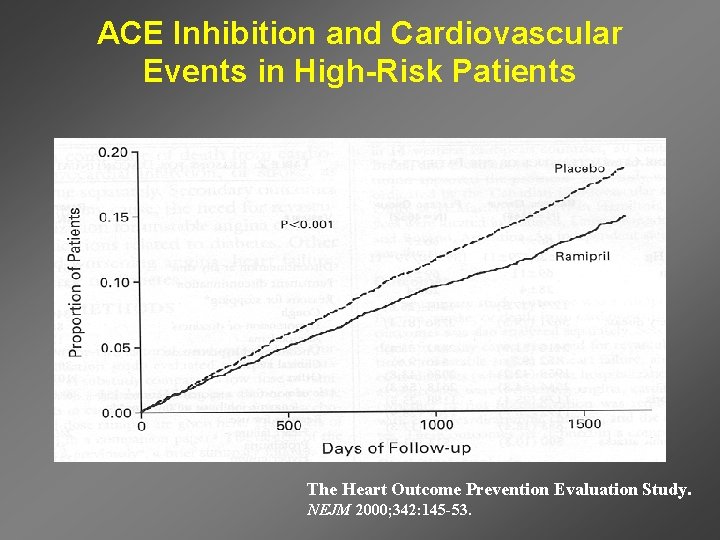

ACE Inhibition and Cardiovascular Events in High-Risk Patients The Heart Outcome Prevention Evaluation Study. NEJM 2000; 342: 145 -53.